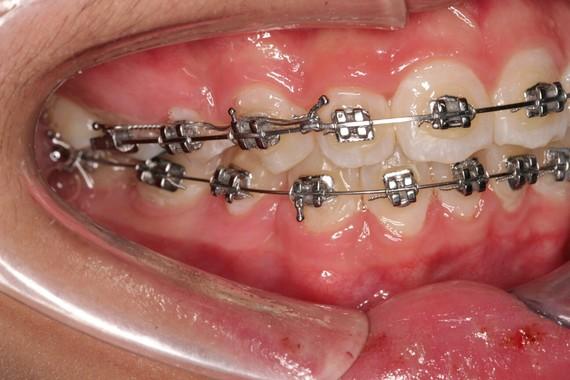

牙弓擴展作為一種常見的牙齒矯正手段,在改善牙齒排列和咬合關系方面發(fā)揮著重要作用。然而,就像任何醫(yī)療操作一樣,牙弓擴展并非毫無風險。了解其潛在的風險以及在擴展過程中需要注意的問題,對于患者和牙醫(yī)來說都至關重要。接下來,讓我們詳細探討這兩個關鍵方面。

牙弓擴展會對牙周組織產(chǎn)生一定的壓力和牽拉。如果擴展的速度過快或力度過大,可能導致牙周膜纖維的損傷,進而影響牙周組織的血液供應。長期下來,這可能會引發(fā)牙齦萎縮、牙槽骨吸收等問題。據(jù)臨床研究表明,不恰當?shù)难拦瓟U展方式可能使牙周疾病的發(fā)生率增加約20%。

在牙弓擴展過程中,牙齒的移動可能會引起牙根表面的壓力變化,導致牙根吸收。尤其是對于牙根較短或牙齒本身存在結構異常的情況,牙根吸收的風險會更高。一項對牙弓擴展患者的跟蹤研究發(fā)現(xiàn),約10%的患者出現(xiàn)了不同程度的牙根吸收。

不恰當?shù)难拦瓟U展可能導致咬合關系的異常。例如,上下牙弓的擴展比例不協(xié)調,可能會造成咬合干擾、咀嚼功能下降等問題。

每個患者的牙弓形態(tài)、牙齒排列、咬合關系等都有所不同,因此需要根據(jù)個體情況制定個性化的牙弓擴展方案。這包括選擇合適的擴展器械、確定擴展的幅度和速度等。